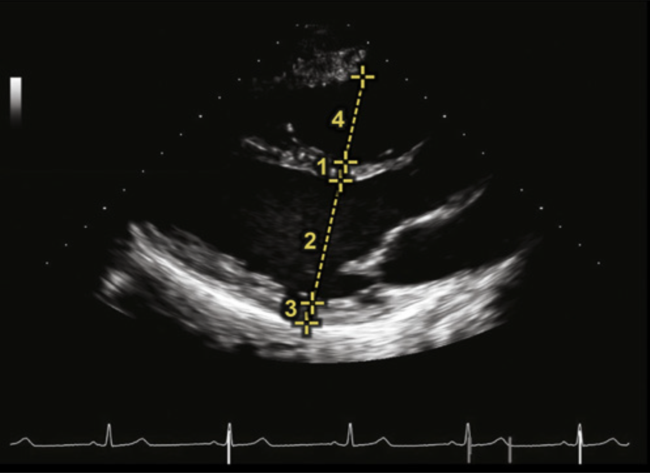

其次,观察心腔的大小。此处根据重症超声评估血流动力学的思维,先从右心评估开始。常规首选心尖四腔心切面(A4C)进行相关测量,在该切面可以测量右心室的上下径和左右径。该方法测量的三尖瓣瓣径通常小于2.8 cm,超过3.9 cm即为重度扩张。中间段直径参考值小于3.5 cm,超过4.2 cm为重度扩张。上下径小于7.9 cm,超过9.2 cm为重度扩张。操作示意图见图2。

图片

图2. 心尖四腔心切面A4C下测量右心室上下径(线段3)和瓣环径(线段1)和中间段内径(线段2)的示意图